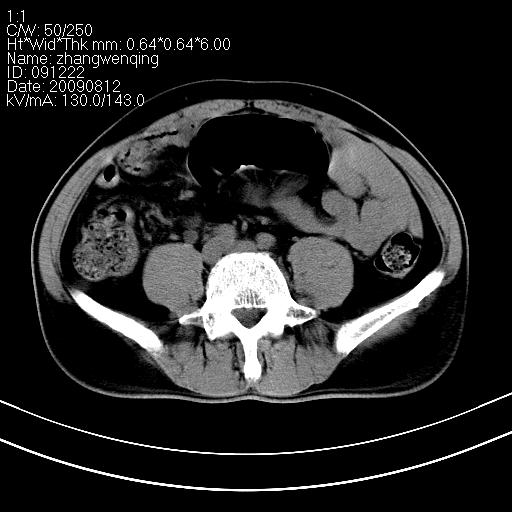

标题: CT21569:M,54Y,右侧中腹部疼痛,IVP示右侧输尿管中下段充盈缺 [打印本页]

标题: CT21569:M,54Y,右侧中腹部疼痛,IVP示右侧输尿管中下段充盈缺

看不清,应打个增强,右侧输尿管扩张,右侧肠系膜上好像占位。

右侧输尿管扩张积水,考虑结石,最好做个增强除外输尿管占位性病变

右输尿管下段扩张积水,壁增厚、边缘不光整,考虑炎性改变

ct21569和ct21569b(增强)结果:阑尾腺癌,侵犯回盲部及输尿管中段。手术切除部分升结肠、回肠及受侵4cm之输尿管,做回-横结吻合,输尿管支架置放术并吻合,术后病理腺癌,阑尾来源可能性大。

右侧输尿管扩张似见软组织密度影,输尿管占位不能排除。